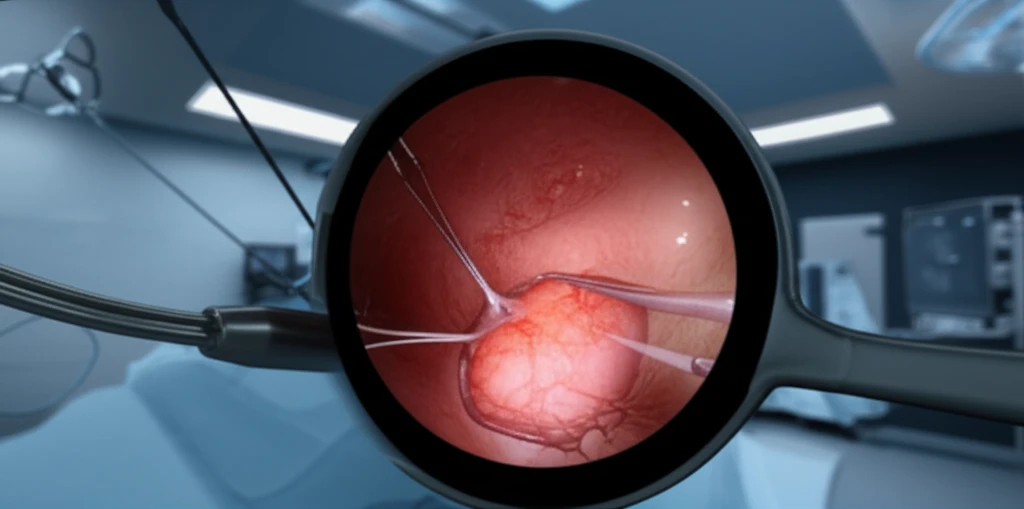

Enter Combined Endoscopic and Laparoscopic Surgery, or CELS, a innovative approach blending the best of both worlds. CELS combines the precision of laparoscopy with the non-invasive nature of endoscopy to safely and effectively remove challenging colon polyps. This method may reduce the need for extensive bowel resections, leading to better patient outcomes and lower healthcare costs.

CELS is a minimally invasive surgical technique used to remove colon polyps that are difficult or impossible to remove through standard colonoscopy. The procedure combines two approaches:

- Endoscopy: A colonoscope, a long, flexible tube with a camera, is inserted through the anus to locate and visualize the polyp.